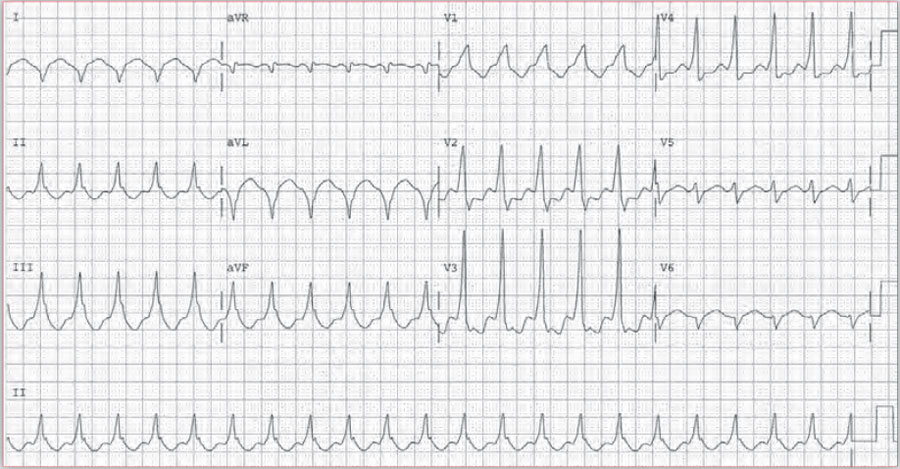

预激综合征合并心房颤动的心电图诊断要点

四个病例带你吃透预激综合征心电图

Case 6: 预激综合征并急性心肌梗死复杂心电图病例讨论